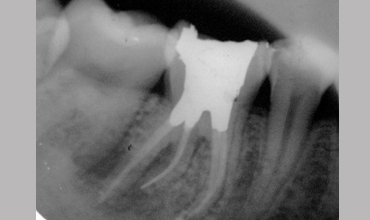

Management Of Radix Entomolaris In Mandibular First Molar